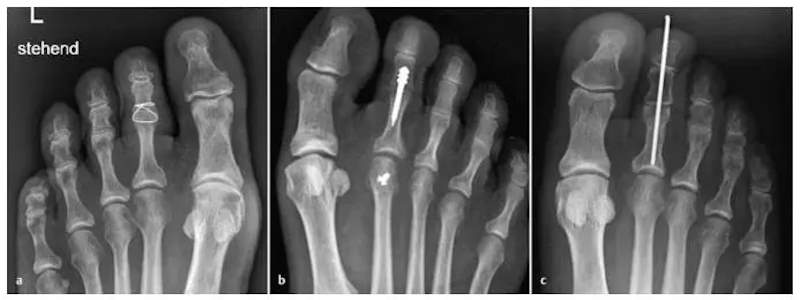

Beispiele für verschiedenartige Osteosynthese Techniken der PIP Arthrodese:

a) Cerclage-Draht b) intramedullärer Kraftträger c) K-Draht